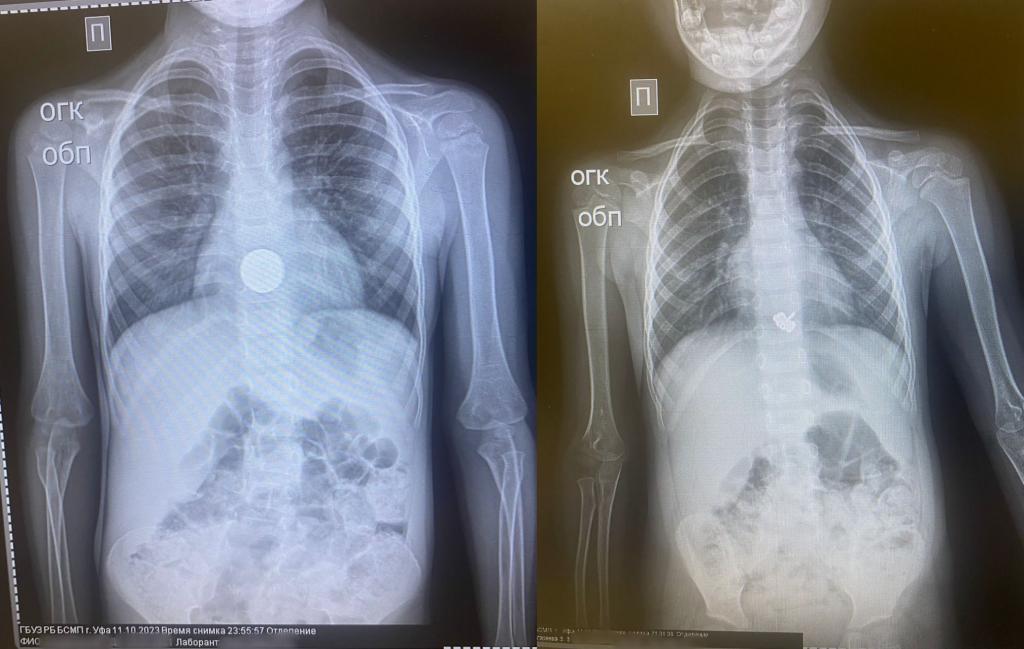

В Башкирии в госпиталь поступили сразу два малолетних пациента с инородными телами в желудке, сообщает Минздрав Башкирии.

Так, четырехлетняя девочка случайно проглотила металлическую заколку в виде стрекозу. Врачи провели экстренную гастроскопию под наркозом и удалили инородное тело за 10 минут. Сейчас ребенок чувствует себя хорошо.

В больницу скорой помощи поступил также трехлетний мальчик, во время игры проглотивший монету. Специалисты также провели экстренную гастроскопию под наркозом. Состояние ребенка на данный момент удовлетворительное.